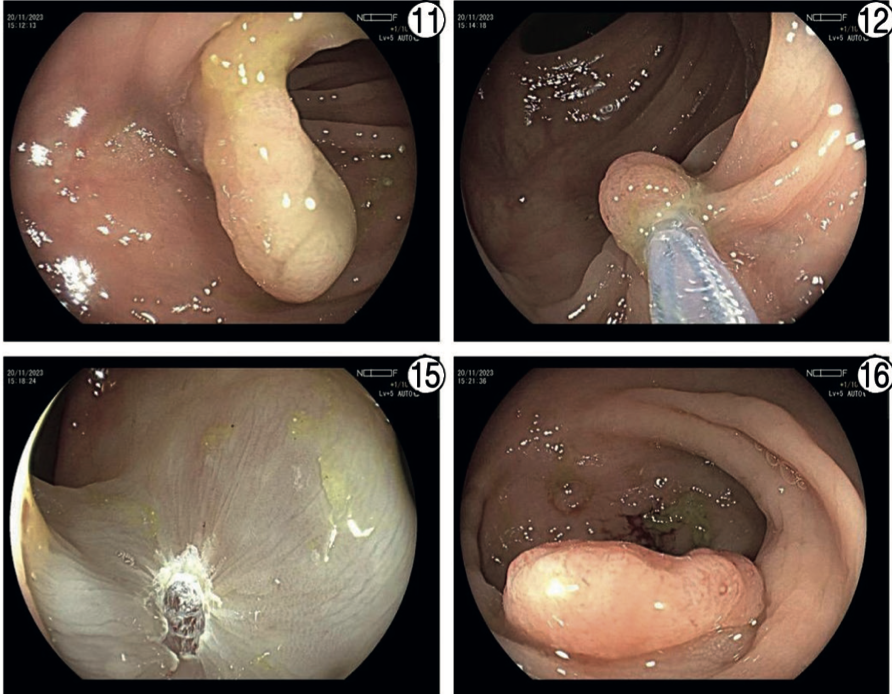

Imágenes y Cirugía

Beatriz Remezal Serrano, Mónica Patricia Rey Riveiro, Pilar Serrano Paz